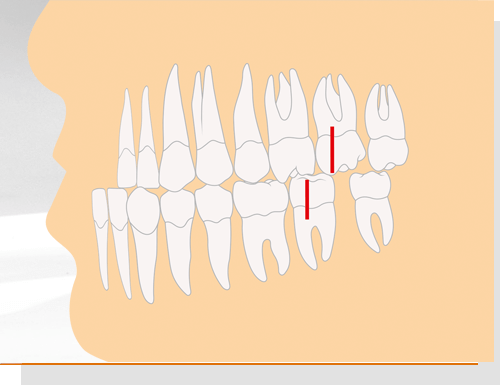

Angle-Klasse 1

Damit wird ein normales Gebiss beschrieben (Neutralbiss): Der vordere Höcker des ersten großen Backenzahns im Oberkiefer trifft genau zwischen die beiden Höcker des gegenüberliegenden ersten großen Backenzahns im Unterkiefer. Nicht nur die Zähne von Ober- und Unterkiefer beißen an den korrekten Stellen aufeinander. Auch das Gesichtsprofil wirkt harmonisch.